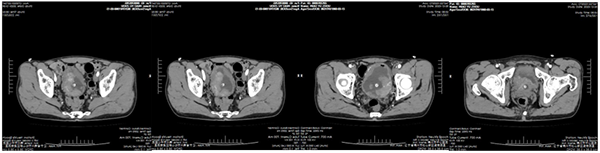

63歲的苗大爺于兩年前無明顯誘因反復出現(xiàn)無痛性肉眼血尿,完善泌尿系超聲,提示膀胱占位病變。得知病情后患者和家屬倍感焦急,輾轉多家醫(yī)院就診治療效果不佳,慕名來到錦州市中心醫(yī)院泌尿外科。

經(jīng)泌尿外科系統(tǒng)診治及全面檢查后,考慮膀胱惡性腫瘤可能性極大。

苗爺爺高齡合并低血紅蛋白癥狀,手術風險極大,級別高。泌尿外科醫(yī)生團隊反復討論了患者的病情,與患者家屬積極溝通后,患者及家屬選擇膀胱全切術。完善膀胱鏡活檢,提示“浸潤性乳頭狀尿路上皮癌”,再次明確了手術指征。

經(jīng)麻醉科協(xié)助圍手術期準備后,于2024年01月02日成功實施了開放式膀胱癌根治術+雙側輸尿管皮膚造口術。